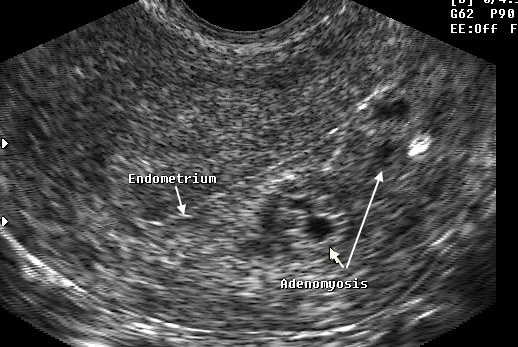

Методы диагностики

Существует несколько способов диагностики аденомиоза. Некоторые из них могут быть довольно дорогими, но именно они обеспечивают точный диагноз и помогают выбрать оптимальное лечение.

- Ультразвуковое исследование (УЗИ) – позволяет выявить увеличение матки, неоднородность миометрия, размытость слоев матки и наличие отдельных очагов. Стенки матки могут иметь различную толщину.